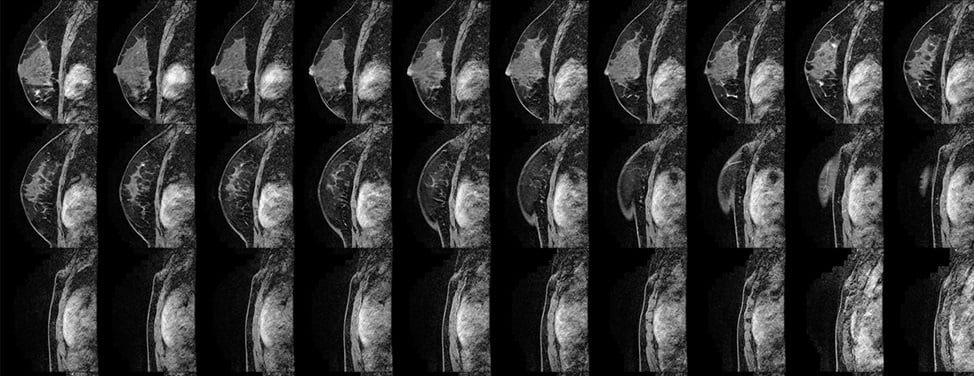

• Mammogram

The goal of screening examinations for early breast cancer detection is to find cancers before they start to cause symptoms. Breast cancers that are detected because they cause symptoms tend to be relatively larger and likely to have spread beyond the breast. In contrast, breast cancers found during screening examinations are more likely to be small and still confined to the breast.